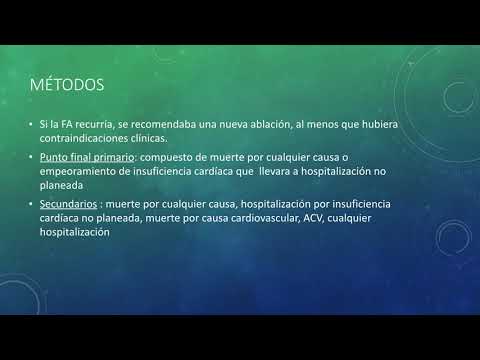

Ablación de la FA en la insuficiencia cardíaca. Estudio CASTLE. Dra. Ana Laura Mori. Residencia de Cardiología. Hospital C. Argerich Buenos Aires